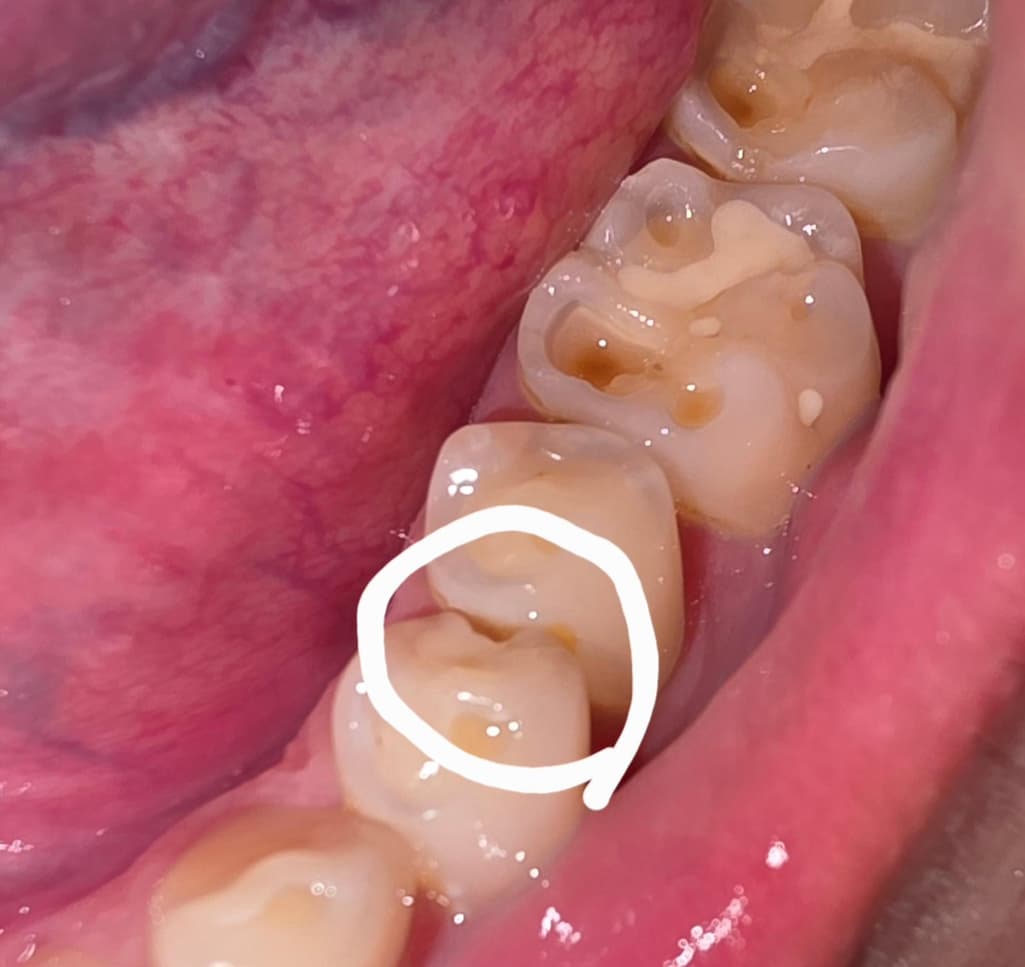

이가 홈이 생겻어요. 어떻게 치료를 하나요?

이가 어느샌가 보니 홈이 생겨져 잇드라구요

여긴 어떻게 치료하나요??....그냥 레진으로도 메꿀수잇나요??

치아가 깨진거 같으니 치과에 가셔서 검진후 인레이치료 또는 크라운 치료를 받으셔야될수도 잇습니다.

치아의 인접면이 충치등으로 인해서 깨지거나 했다면 해당부위에 음식물이 자주 끼게 되어 충치가 더 커질수 있습니다. 치료를 해야 하는데 레진으로 인접면을 치료할경우 치아의 모양을 형성해주기 어려울수 있습니다.

이런경우에는 인레이나 크라운의 보철치료를 하게 됩니다.

이전에 떼운게 깨졌네요 치과가서 해당 부위 체크해보고 동일 재료로 떼울 수 있다면 떼우면 될 것 같습니다